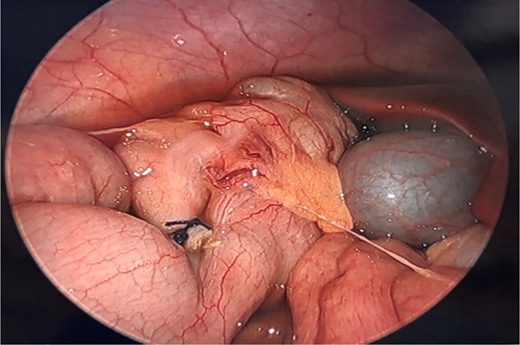

Image depicting a moderate amount of serous fluid lateral to the right colon and above the liver as well as a ligated appendix base and stump.